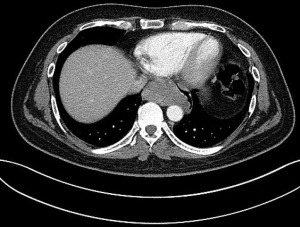

Patient 1 was a 41-year-old man with a history of primary cerebral diffuse large B-cell lymphoma diagnosed 1 year earlier and treated with chemotherapy. At early follow-up CT imaging, a 73 mm tumor located in the subcarinal space was diagnosed (Figure 1).

It showed high fludeoxyglucose (FDG) activity on positron emission tomography-CT (PET/CT). A lymphoma recurrence was suspected and oesophgao-gastro-duodenoscopy (OGD) followed by endoscopic ultrasound (EUS) were performed. It described a tumor located at 32 cm from the incisors and originating from the submucosal plane. EUS-fine-needle aspiration (FNA) was performed but could not establish a diagnosis. A surgical biopsy via video-assisted thoracoscopic surgery (VATS) was performed. Histopathological examination revealed a leiomyoma of the oesophagus. A posterolateral thoracotomy was performed in the 7th intercostal space and the leiomyoma was freed from the oesophagus in its muscular layer. Enucleation was possible without oesophageal resection. Final histopathological examination confirmed the diagnosis of leiomyoma, measuring 82 mm. After an uneventful postoperative stay, the patient was discharged on postoperative day 7.